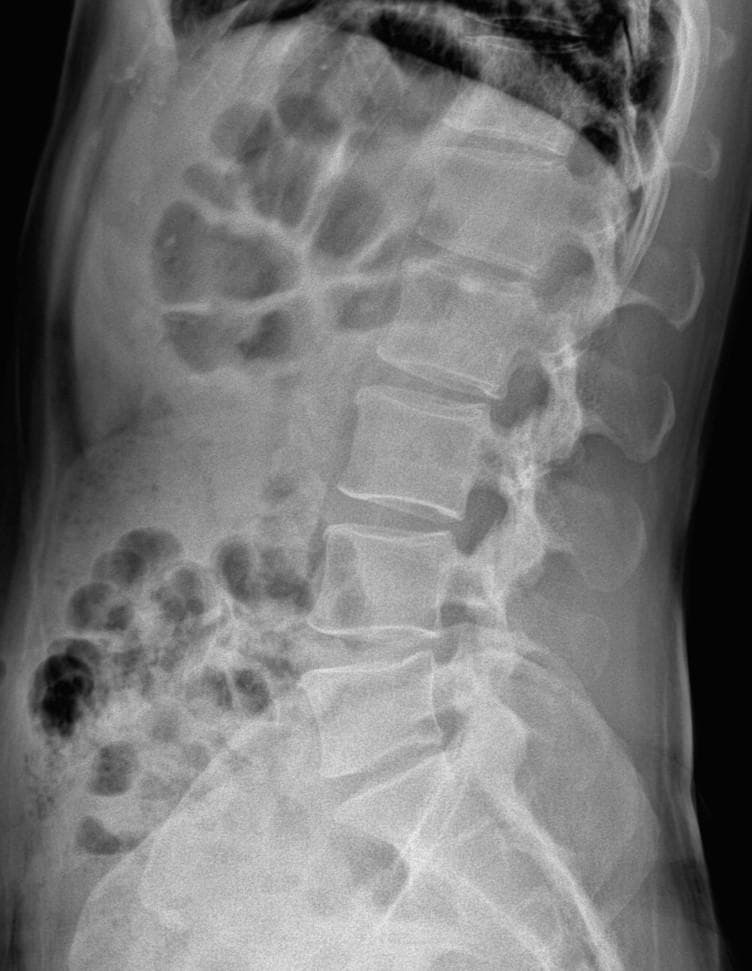

• 3번 째 사진

엑스레이 상에서는 요추 배열이 전반적으로 잘 유지돼 보입니다. 마나 일부 요추 간격이 좁아진 부위가 있어 보입니다. 말씀하신 것처럼 특정 동작에서 찌릿 혹은 뜨끔하거나, 최근 뻐근함이 생기는 건 디스크 초기나 근육, 인대 긴장에서도 나타날 수 있습니다.

허리의 커브가 줄어들어있다는것을 제외하고는 크게 문제가될만한 부분은없는데요 통증과불편감이 지속된다면 MRI와같은 정밀검사가 필요할수있습니다

사진상 요추 사이의 간격이 다소 좁아 보이며 간격이 좁다는 것은 퇴행성 변화를 의미하며 척추의 정렬 또한 큰 전위는 없어 보이나 허리 곡선이 정상보다는 조금 감소한 상태로 이러한 경우 근육의 긴장이나 만성적인 통증이 발생할 수 있습니다.

• 엑스레이 검사를 통해서는 현실적으로 뼈 위주의 평가만 가능하며 정밀하고 자세하게 평가를 내리는 것은 어렵습니다. 올리신 엑스레이 사진들에는 특별히 문제가 있다고 볼만한 소견이 크게 있어보이거나 하지는 않습니다.

우선 현재로썬 척추와 척추 사이인 디스크 공간이 좁지는 않아보이지만 다소 요추의 커브가 감소되어 있어 보입니다.